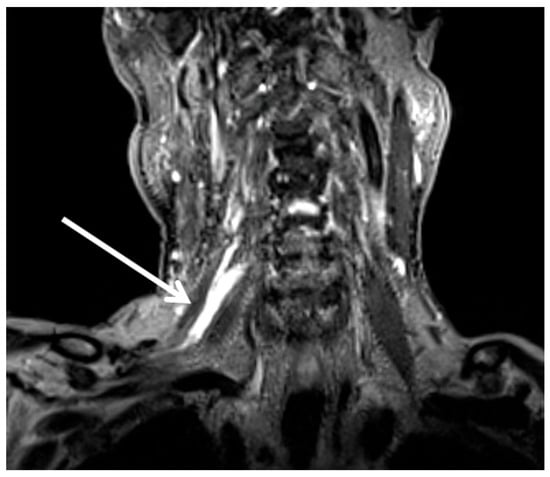

2. Case Presentation